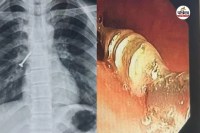

विवाद बढ़ने पर युवक ने गुस्से में आकर लोहे की रॉड से महिला के सिर पर वार कर दिया। हमले में गंभीर रूप से घायल महिला रचना जाट (40) पत्नी भूपेंद्र जाट निवासी कल्याणपुर सायटा की मौके पर ही मौत हो गई।

चिकित्सकों ने मृतका के सिर में गहरी चोट होना बताया है। चिकित्सालय सूत्रों के अनुसार सुबह करीब 9.30 से 10 बजे कल्याणपुर सायटा के लोग एक महिला को अचेत में चिकित्सालय लेकर आए।

परीक्षण के दौरान महिला के सिर पर किसी वस्तु के चोट के निशान मिले थे। जांच में मृत घोषित होने पर शव को जिला चिकित्सालय की मोर्चरी में रखवा दिया।